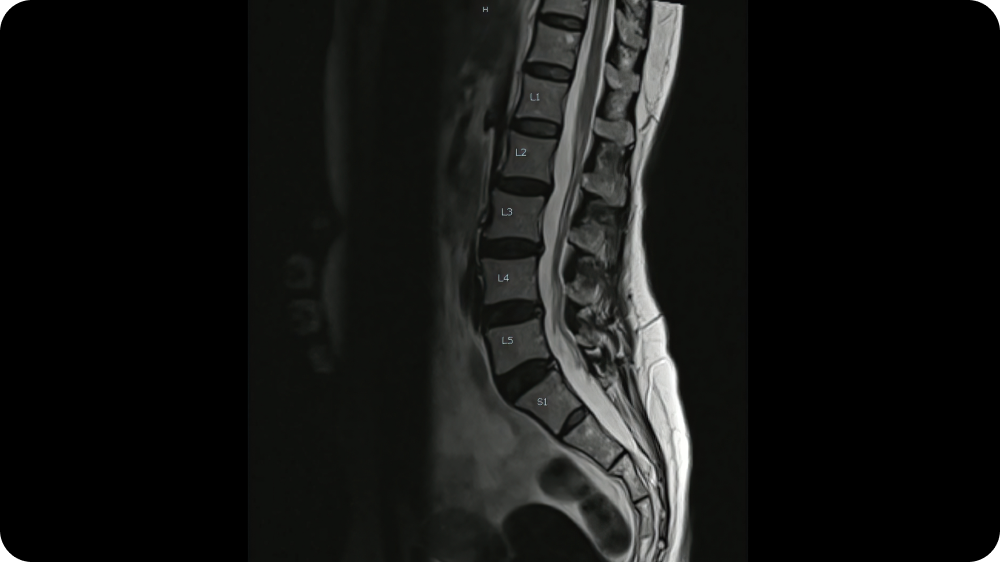

椎間板内部の損傷を丁寧に確認

当クリニックでは、MRIで評価できる情報に加え、針で椎間板内に造影剤を入れ、造影剤の広がり方から椎間板の損傷具合を細かく評価する検査を行います。

脊柱管狭窄症

加齢に伴う椎間板の変性や椎間関節の変化、靱帯(じんたい)の肥厚などが重なり、神経の通り道(脊柱管)が狭くなることで生じる病気です。

腰椎すべり症

椎間板や関節などの加齢変化に伴って腰椎(ようつい)が前方にずれ、神経を圧迫する病気です。

腰椎椎間板ヘルニア

椎間板は外側の線維輪と内側の髄核から構成されています。線維輪に亀裂が生じ、髄核の一部が外へ突出すると、神経を刺激・圧迫し、腰痛や坐骨神経痛、足のしびれなどの症状が現れることがあります。